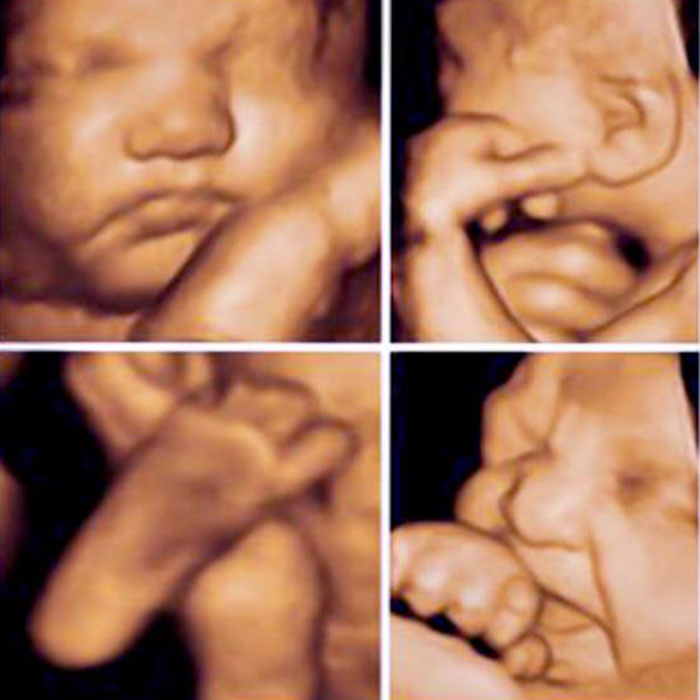

4D ve 5D Obstetrik Ultrasonografi

3D ultrasonografik görüntülerin video formatında gösterilmesi ile 4D görüntüler elde edilir. 4D obstetrik ultrasonografik incelemeler için en uygun inceleme aralığı 24. Hafta ile 32.hafta aralığı kabul edilmektedir. Gelişen HD teknolojisi ile fetüsün keskin yüz hatları ve derinlik algısı ile gerçekle özdeşmesi tama yaklaşmaktadır. Bu yeni teknoloji 5D canlı ultrason olarak tanımlanmaktadır.